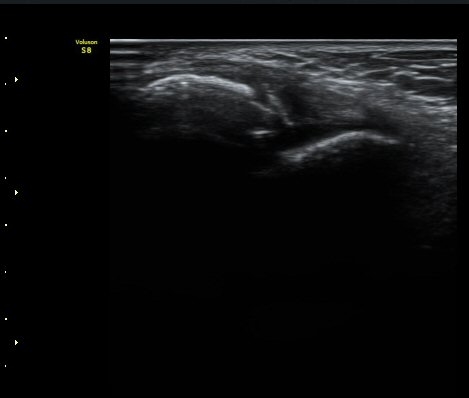

3ÁÖ ÈÄ ÃßÀû°Ë»ç»ó °üÀý³» ºÎÁ¾ÀÌ ¼Ò½ÇµÇ°í(±×¸² 4). Àü°Å°ñºñ°ñÀδëÀÇ Àú¿¡ÄÚ ºÎÁ¾ÀÌ

°¨¼ÒÇÏ°í °ß¿­°ñÀý °ñÆíÀº ºñ°ñ °¡±îÀÌ À§Ä¡Çϰí ÀÖ´Ù(±×¸² 5, 6).

ÃÊÀ½ÆÄ Åõ½ÃÇÏ ºÎÇϰ˻翡¼­ ºñ°ñ°ú ÀδëºÎÂøºÎ¿Í  ºñ°ñ°ú °Å°ñ»çÀ̰¡ ¹ú¾îÁöÁö ¾Ê´Â´Ù

(樨毢 2).